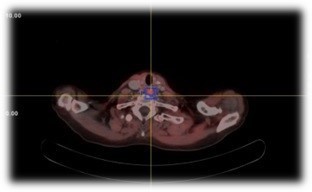

Two months postoperatively, PET-CT revealed persistent hypermetabolic cervical and mediastinal lymphadenopathy and a retroesophageal prevertebral nodule (Figure 3). Due to extensive prior surgeries and persistent disease, radiotherapy was initiated following multidisciplinary consensus.

Figure 3: PET-CT 18FDG (hyperactive cervical and mediastinal lymph nodes and a prevertebral retroesophageal nodule).